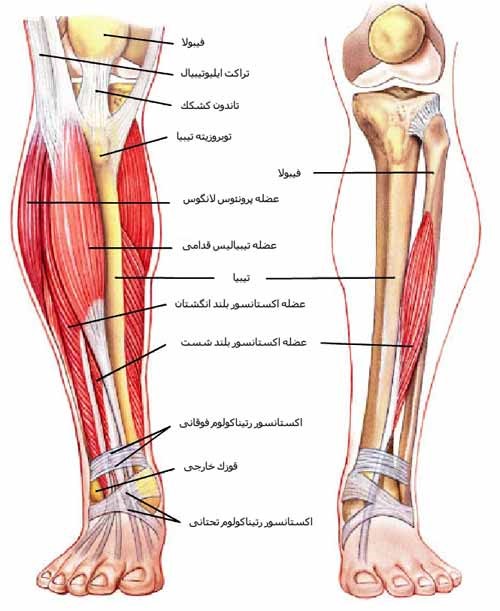

قیمت: 68٬000 تومان - دسته بندی فایل: پاورپوینتپاورپوینت عضله و مفصل و نیروهای تاثیرگذار بر آن

فروش ویژه پاور پوینت حرفه ای عضله و مفصل و نیروهای تاثیرگذار بر آن با تخفیف استثنایی فقط 72384 تومان تعداد اسلاید: 39 اسلاید